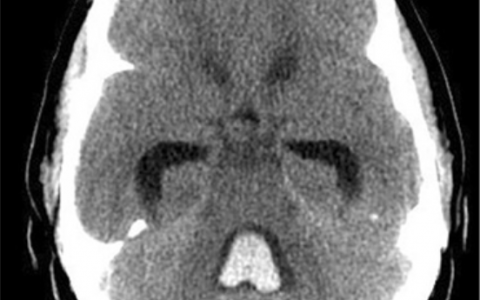

A 38-year-old woman at 34 weeks’ gestation is admitted to the ICU with altered mental status and jaundice. Right upper quadrant ultrasound reveals a fatty liver.

与HELLP综合征(溶血、肝功能升高、血小板计数降低)和重度子痫前期的鉴别可能需要肝活检。急性脂肪肝与肝功能障碍有关,包括合成功能。氨和转氨酶水平较高,低血糖较多,常见弥散性血管内凝血。首选的治疗方法是胎儿娩出和支持治疗。熊去氧胆酸适用于治疗妊娠期肝内胆汁淤积症。